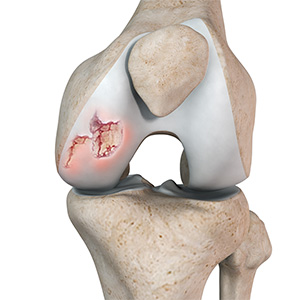

Chondral or Articular Cartilage Defects

The articular or hyaline cartilage is the tissue lining the surface of the two bones in the knee joint. Cartilage helps the bones move smoothly against each other and can withstand the weight of your body during activities such as running and jumping. Articular cartilage does not have a direct blood supply to it, so has less capacity to repair itself.

Osteochondral Defect of the Knee

An osteochondral defect, also commonly known as osteochondritis dissecans, of the knee refers to a damage or injury to the smooth articular cartilage surrounding the knee joint and the bone underneath the cartilage. The degree of damage may range from a rupture of the cartilage to a slight crack of the bone to a piece of the bone breaking off within the joint.